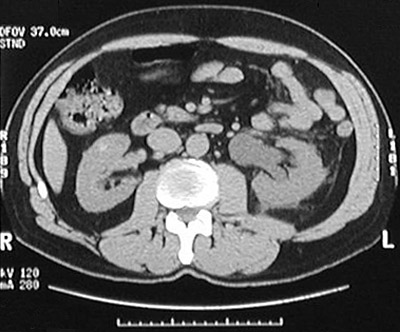

The left ureter seen in this abdominal CT scan exhibits hydroureter as a consequence of obstruction from passage of urinary tract calculi.